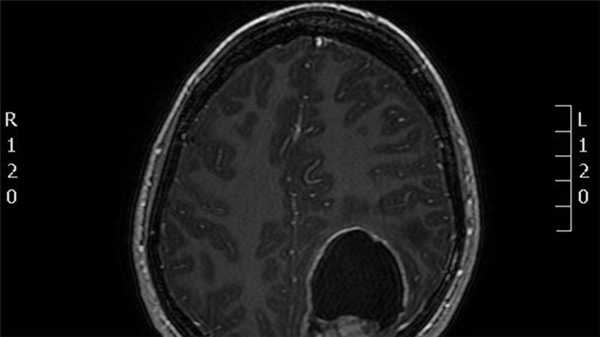

Эпендимома задней черепной ямки у ребенка

Эпендимома головного мозга чаще образуется в задней черепной ямке. Во многих случаях характеризуется медленным ростом, отсутствием прорастания в окружающие церебральные ткани. Однако по мере роста новообразования оно может вызвать масс-эффект — сдавление головного мозга. Метастазирование эпендимомы происходит преимущественно по ликворным путям и, как правило, не выходит за пределы ЦНС. Наиболее часто отмечаются ретроградные метастазы в спинной мозг.

Обычно это хорошо отграниченные и доброкачественные опухо- ли (хотя встречаются и злокачественные эпендимомы). Они часто возникают в дне IV желудочка (в 60-70% случаев располагаются инфратенториально, всегда вблизи IV желудочка, на их долю приходится 25% от всех опухолей области IV желудочка). Эпендимомы задней черепной ямки у детей часто являются анапластическими, при этом имеется больший риск распространения по нервной трубке. Хотя гистологически они не выглядят такими злокачественными, как медуллобластомы, они имеют худший прогноз из-за того, что они имеют тенденцию врастать в obex(задвижку), что препятствует их полному удалению. Субэпендимомы: для них типично расположение в передних отделах боковых желудочков или в задней части IV желудочка, выраженная роль субэпендимарных глиальных клеток. Нередко обнаруживаются на аутопсиях, подлежат хирургическому лечению в редких случаях.

КТ/МРТ:

Обычно обнаруживают объемное образование в дне IV желудочка, часто с окклюзионной гидроцефалией.